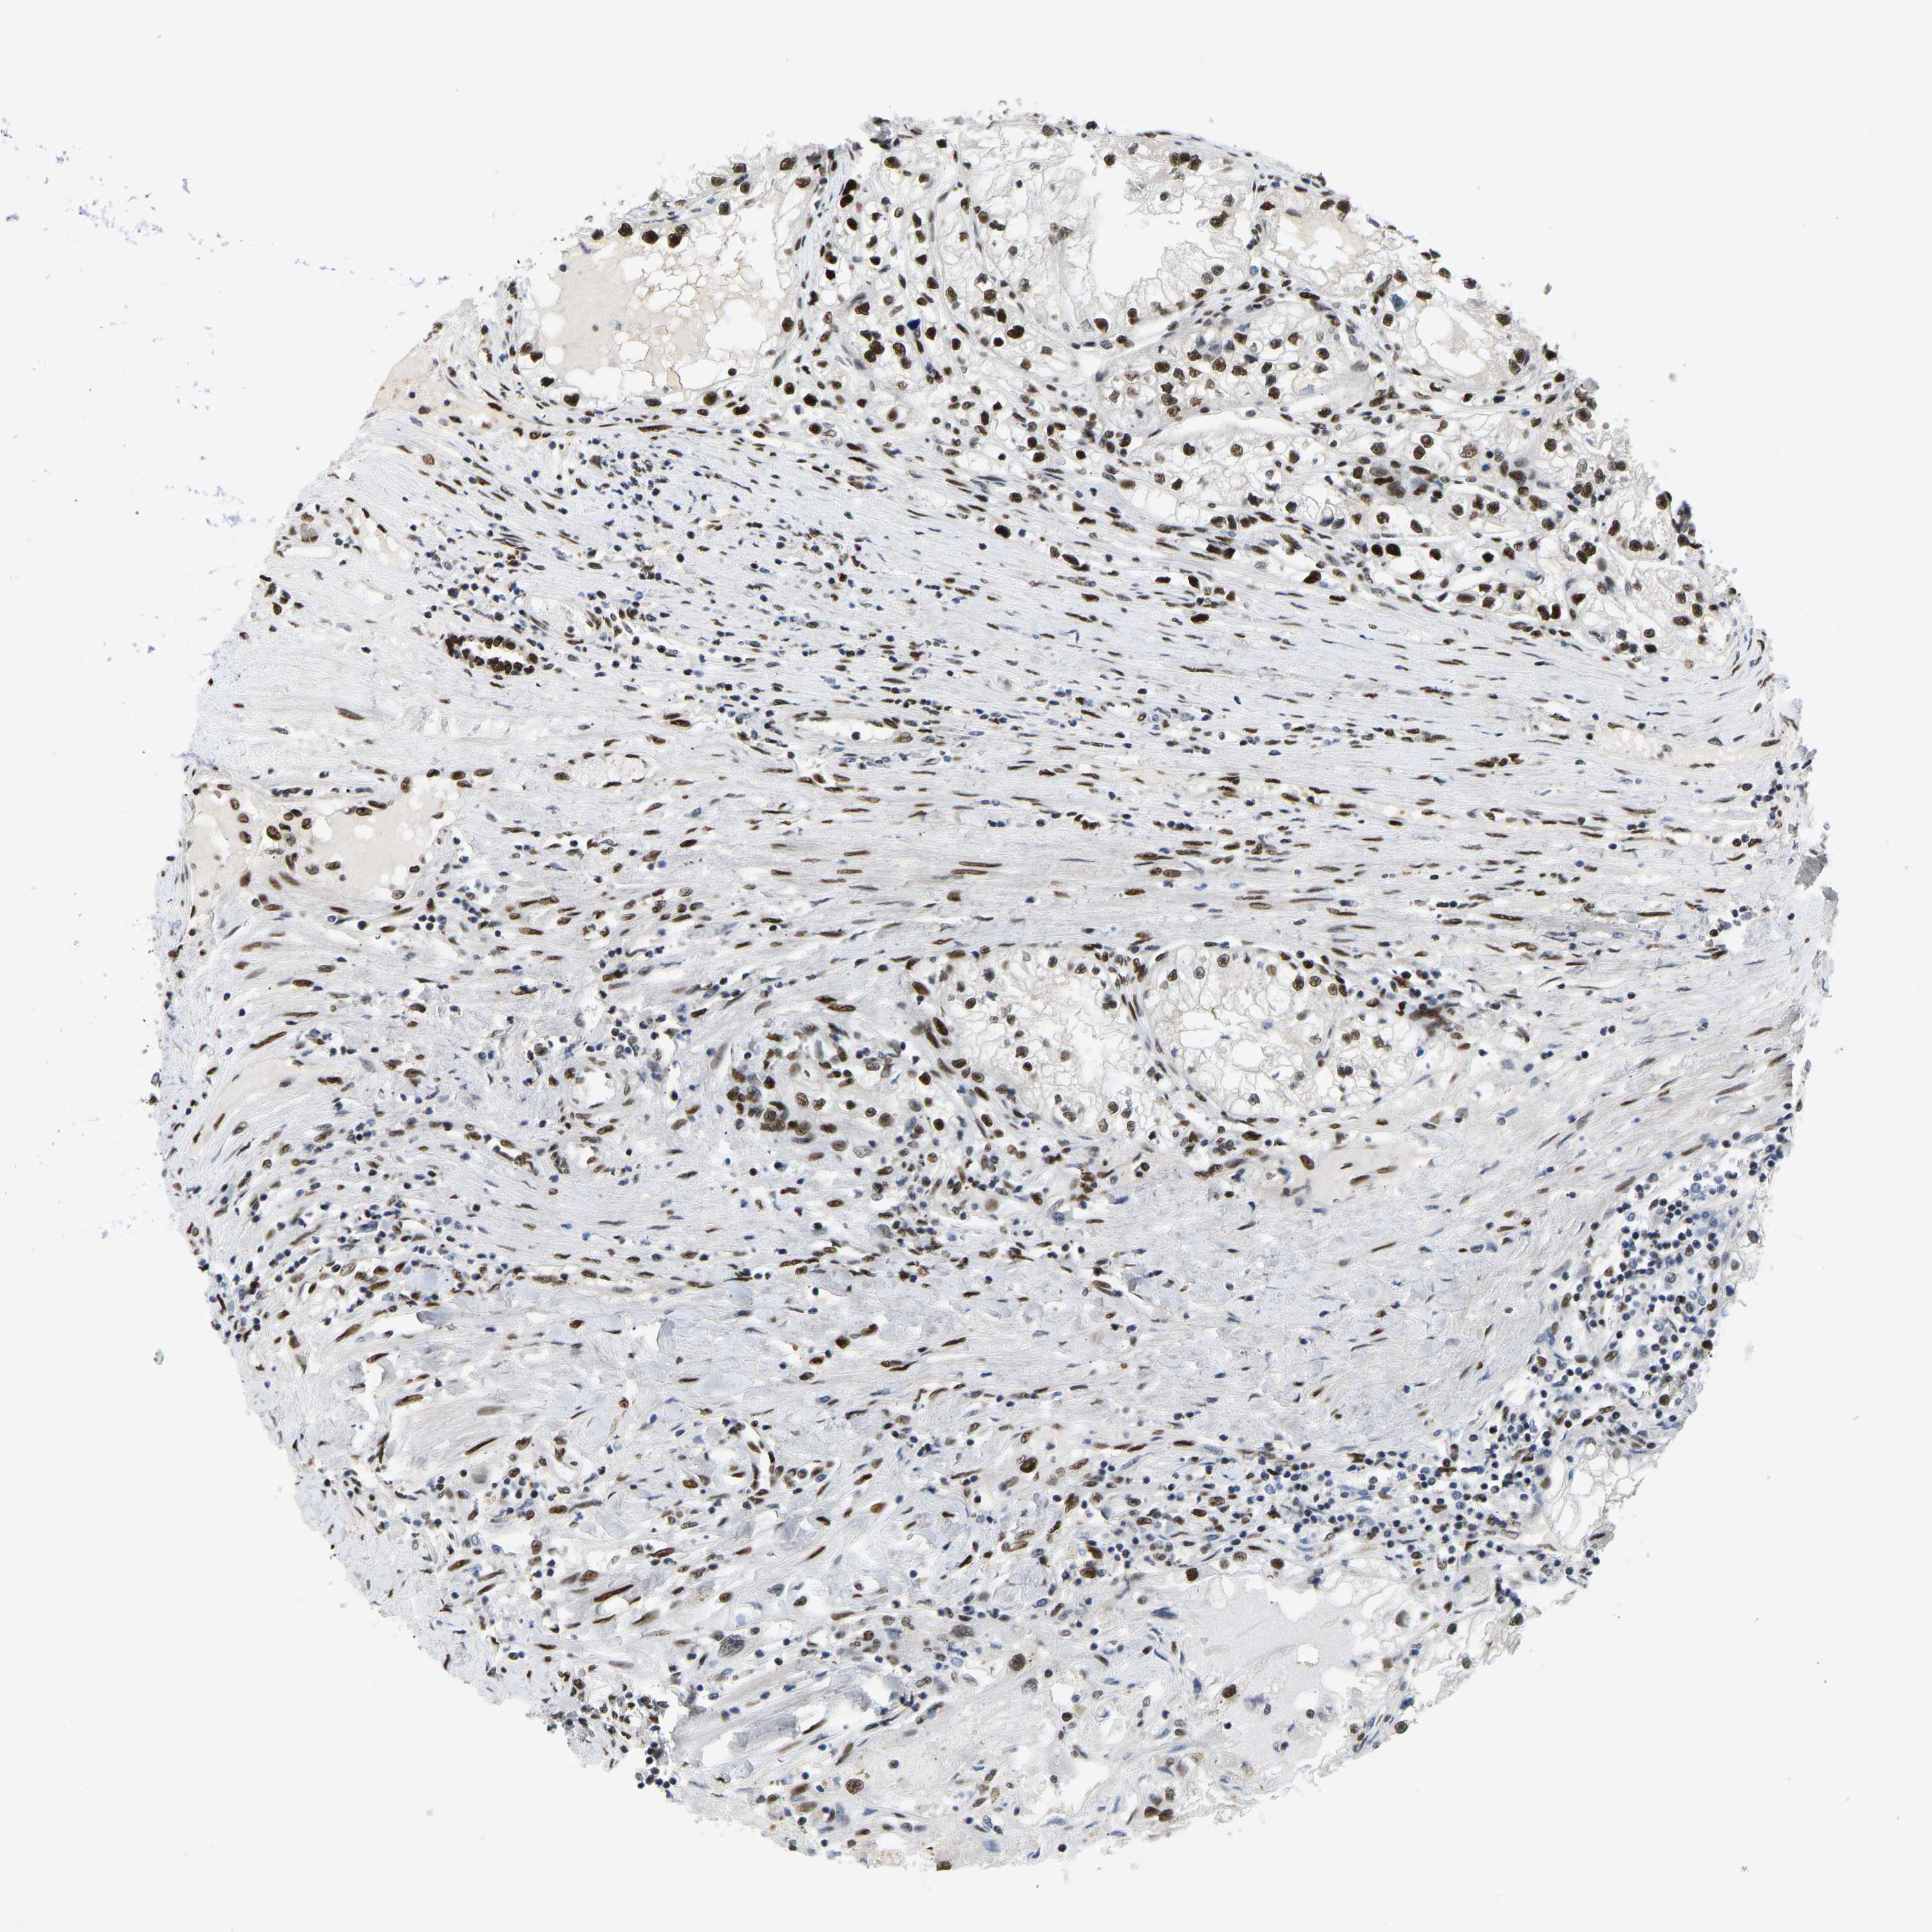

KIDNEY RENAL CLEAR CELL CARCINOMA (VALIDATION) - Interactive survival scatter ploti

The Survival Scatter plot shows the clinical status (i.e. dead or alive) for all individuals in the patient cohort, based on the same data that underlies the corresponding Kaplan-Meier plots. Patients that are alive at last time for follow-up are shown in blue and patients who have died during the study are shown in red.

The x-axis shows the expression levels (FPKM) of the investigated gene in the tumor tissue at the time of diagnosis. The y-axis shows the follow-up time after diagnosis (years). Both axes are complimented with kernel density curves demonstrating the data density over the axes. The top density plot shows the expression levels (FPKM) distribution among dead (red) and alive patients (blue). The right density plot shows the data density of the survived years of dead patients with high and low expression levels respectively, stratified using the cutoff indicated by the vertical dashed line through the Survival Scatter plot. This cutoff is automatically defined based on the FPKM cutoff that minimizes the p-score. The cutoff can be changed by dragging the vertical line or by entering a cutoff value in the square labeled "Current cut-off".

Under the Survival Scatter plot the p-score landscape (black curve; left axis) is shown together with dead median separation (red curve; right axis). Dead median separation is the difference in median mRNA expression between patients who have died with high and low expression, respectively. It is calculated as follows: median FPKM expression of dead patients with high expression - median FPKM expression of dead patients with low expression. This is intended to aid the user in visually exploring custom cutoffs and the associated p-scores and dead median separation.

Individual patient data is displayed and can be filtered by clicking on one or more of the category buttons on the top of the page. Categories describing expression level and patient information include: high, low, alive, dead, female, male and tumor stages. The scale of the x-axis can be toggled between linear and log-scale by clicking on the "x log" button. Mouse-over function shows TCGA ID, patient information and mRNA expression (FPKM) for each patient.

& Survival analysisi

Kaplan-Meier plots summarize results from analysis of correlation between mRNA expression level and patient survival. Patients were divided based on level of expression into one of the two groups "low" (under cut off) or "high" (over cut off). X-axis shows time for survival (years) and y-axis shows the probability of survival, where 1.0 corresponds to 100 percent.

FOXK1 is not prognostic in Kidney Renal Clear Cell Carcinoma (validation)

Best expression cut offi

: 9.13

P scorei

N/A

Average pTPM 9.9

Number of samples 100